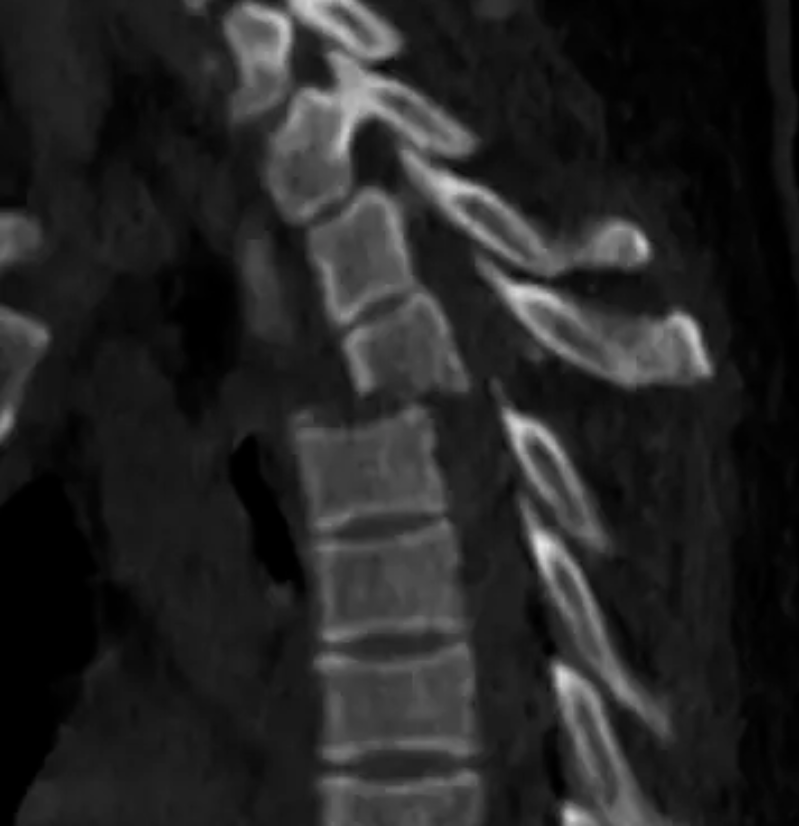

△胸4椎體爆裂性骨折伴脫位。

胸12椎體爆裂性骨折,骨折碎塊壓迫椎管。